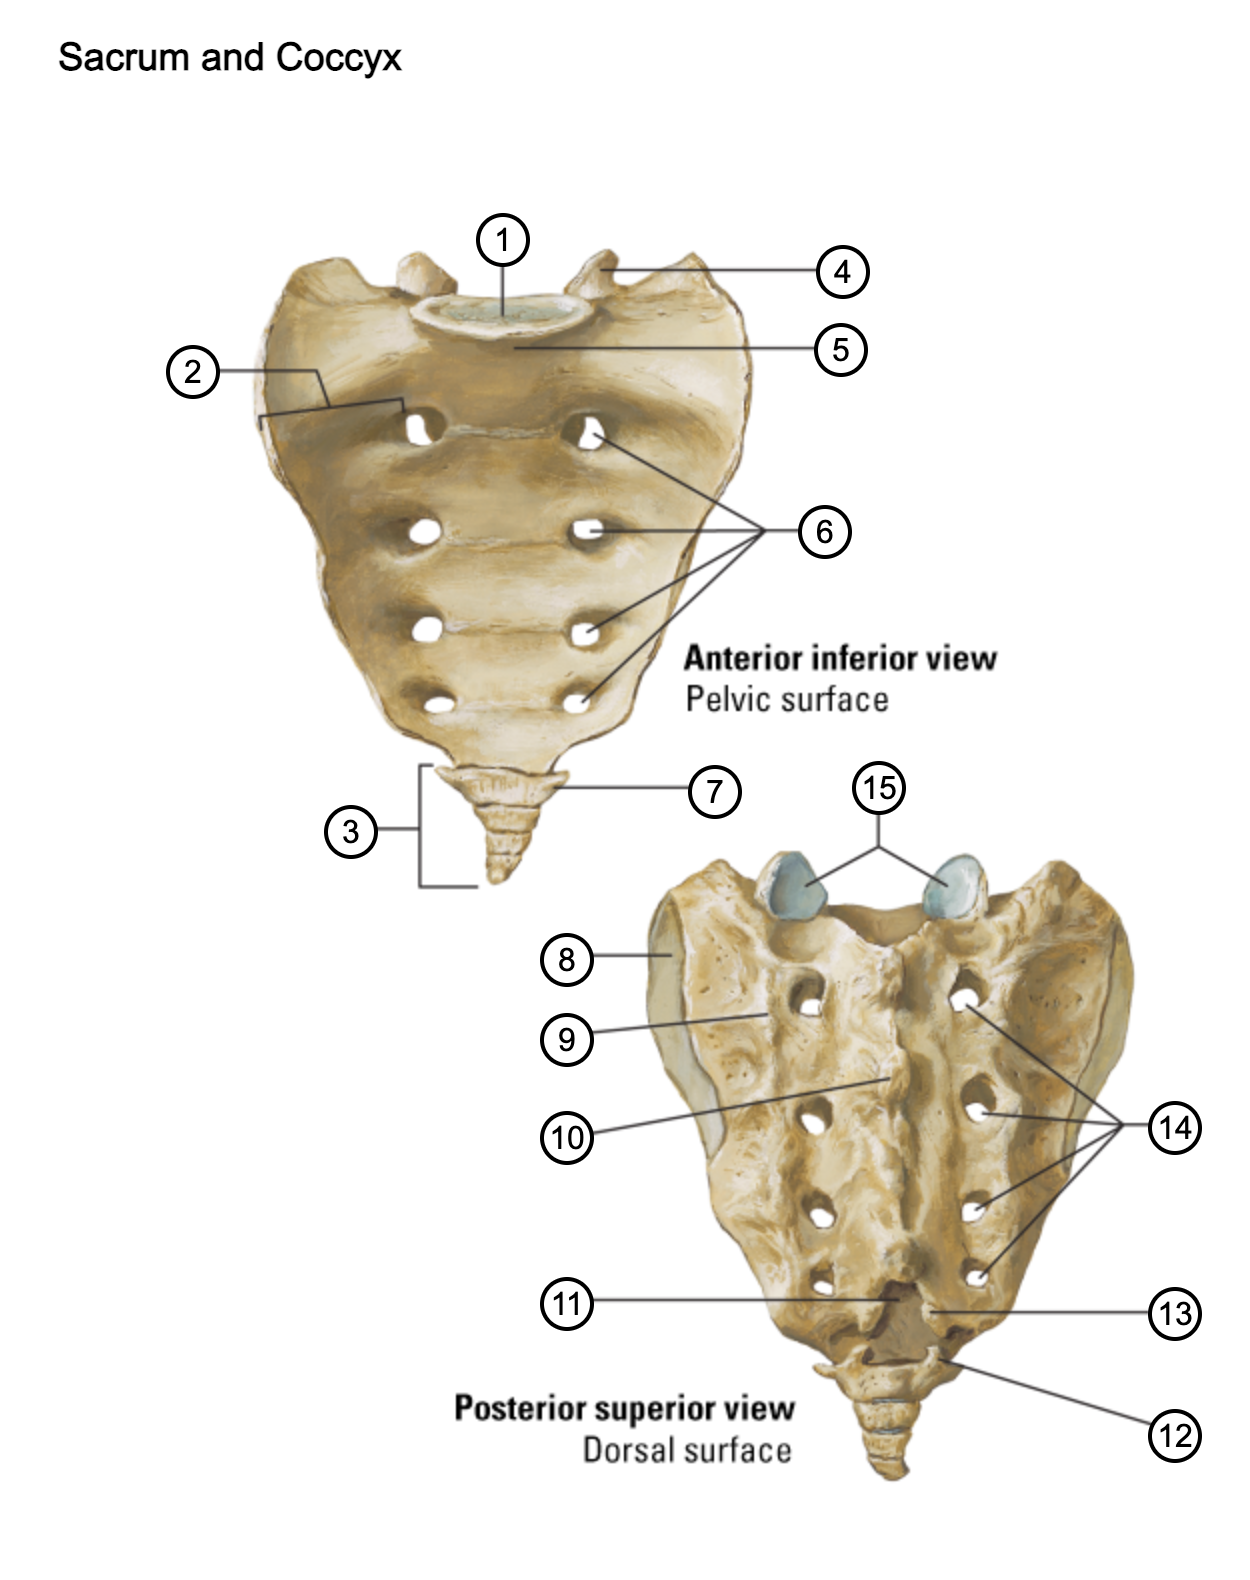

1

lumbosacral articular surface

2

ala of sacrum

3

coccyx

4

superior articular process

5

promontory

6

anterior sacral foramina

7

transverse process of coccyx

8

auricular surface

9

lateral sacral crest

10

median sacral crest

11

sacral hiatus

12

coccygeal horn

13

sacral horn

14

posterior sacral foramina

15

facets of superior articular processes